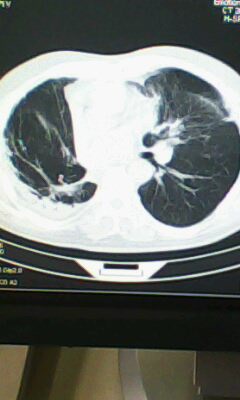

标题: CT25675:男 71 肺癌部分切除术后 3年 [打印本页]

标题: CT25675:男 71 肺癌部分切除术后 3年

两肺感染性病变,右侧肺膨胀不全,左侧上叶结节影及左侧颈部淋巴结肿大建议复查。

1)两肺感染性病变。2)右侧胸膜增厚。3)冠状动脉及主动脉钙化。

右肺炎症,左肺炎症。

两肺感染性病变\\右侧胸膜增厚

2.左肺炎症。

术后改变,双肺内纤维索条影考虑与放疗有关。